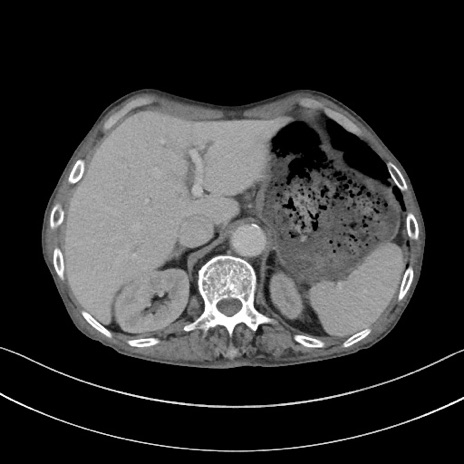

症例3(横断像)

【症例】 70歳代男性

【主訴】右鼠径部腫瘤、疼痛

【現病歴】本日朝より上記主訴あり、受診。

【既往歴】膀胱癌にて膀胱全摘、両側尿管皮膚瘻

【データ】WBC 5600、CRP 0.56